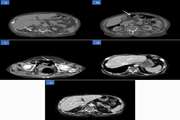

A rare case of hepatic portal venous gas (HPVG) diagnosed as emphysematous cystitis in an elderly diabetic dialysis patient 1403/12/25 - 12:00